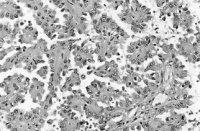

Mikroskopisch wird das Bild von klarzelligen, zum Teil drüßenschlauchähnlichen (tubulären) oder soliden Strukturen dominiert (Abbildung 2). Die hellen Zellen sind pflanzenähnlich und mit glykogen gefüllt. Im Weiteren finden sich Nekrosen und Blutungen.